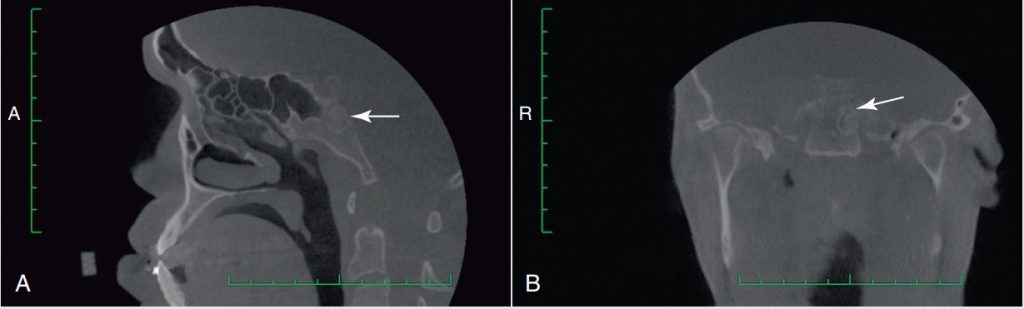

- Kết quả tình cờ trên phim CBCT: tổn thương ở nền sọ (Hình 2-17).

- Bệnh nhân được gửi đi chụp MRI; tổn thương kích thước 12,0 × 8,5 × 8,5 mm, khả năng có nguồn gốc sụn (chondroid origin) và không xâm lấn.

- Đề nghị tái khám và chụp lại sau 6 tháng; đã được bác sĩ chẩn đoán hình ảnh cho phép phẫu thuật chỉnh hình xương hàm.